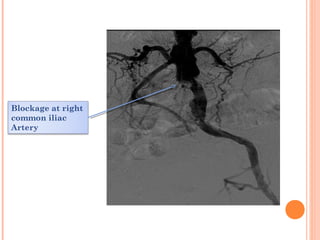

ANGIOGRAPHY

produces a road map of the blood

vessels.

Shows site ,extent and severity of

blockage

In Thrombangitis Oblitrans

corkscrew apperance

Distal run-off

inverted tree/ spider leg apperance

Corrugated , ripped artery

TYPES

Free flush

Selective

Collaterals

Blockage at right

common iliac

Artery